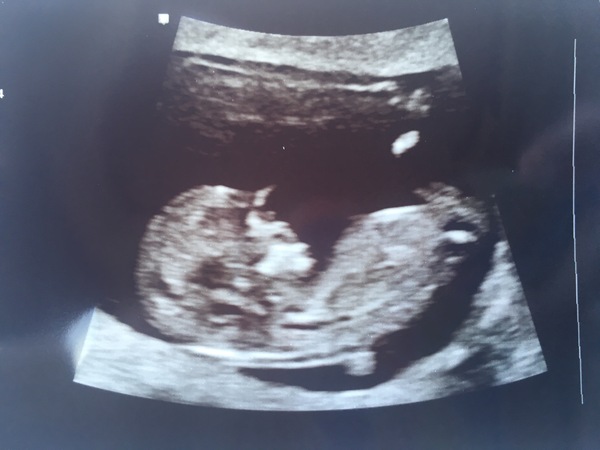

Our little bean today at 12+1 ❤

So cute Oliver!!!

Lovely to see scan pics xx